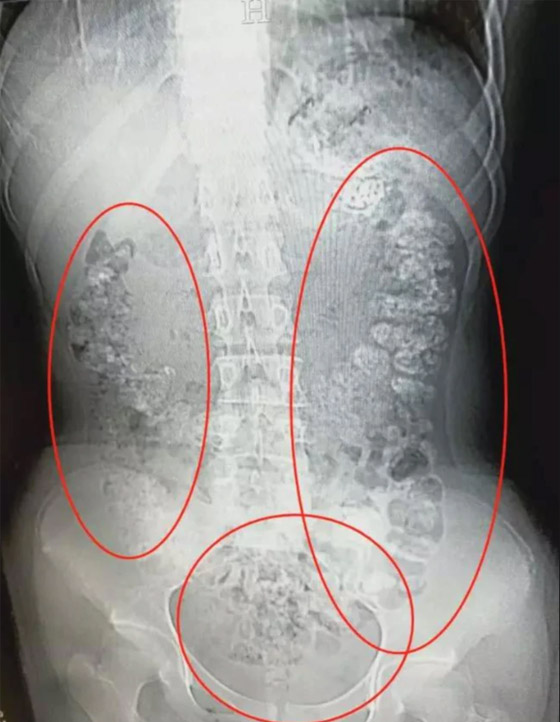

وتم نقلها الشهر الماضي إلى مستشفى رويجين، حيث تم تسجيل مستويات السكر في الدم لديها بما يقرب من 25 مرة أعلى من المعتاد، وفقا للتقرير. وذكر التقرير أنه تم وضع المراهقة على جهاز التنفس وتلقت غسيل الكلى قبل الاستيقاظ من الغيبوبة بعد خمسة أيام. وكشف التقرير أنه بحلول يونيو/حزيران، بدا أن المراهقة تمتثل للشفاء وخرجت من المستشفى.